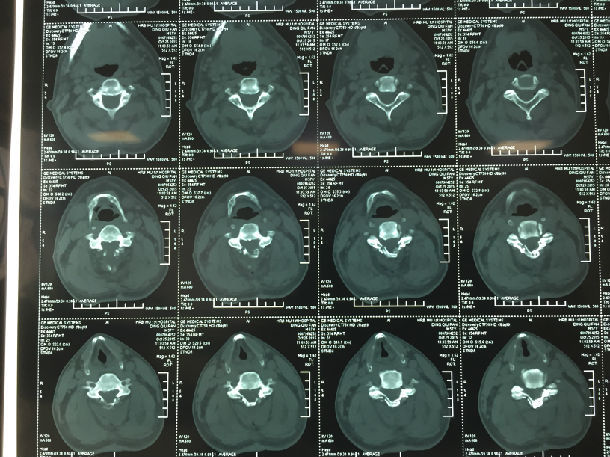

手术前-多节段颈椎间盘突出/黄韧带肥厚/颈椎管狭窄-脊髓损伤

手术前-颈髓明显受压伴脊髓损伤